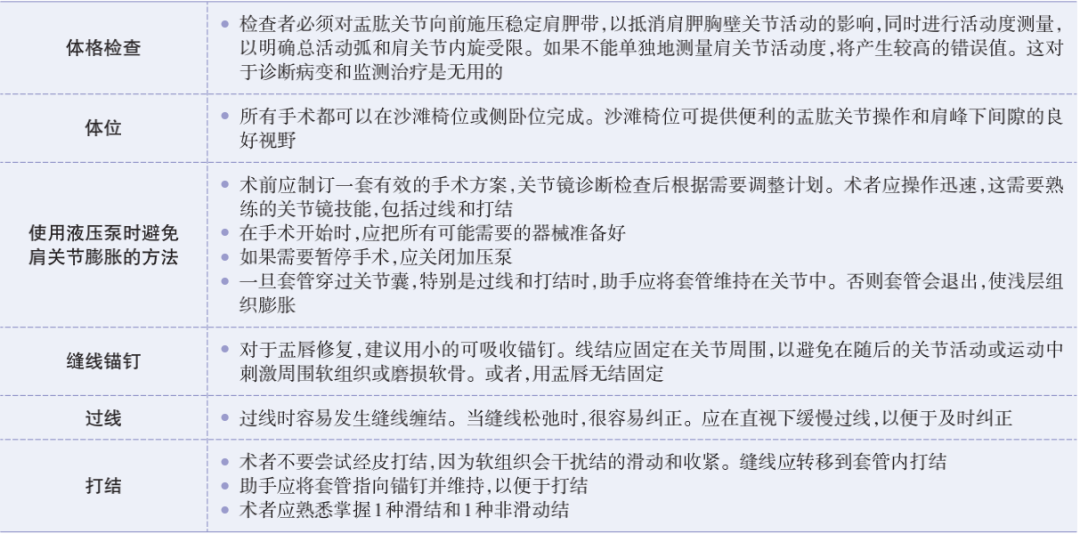

术前准备体位

6 种手术入路

3. 低位前方入路:位于肩胛下肌腱上缘的正上方;用于锚钉置入、关节囊紧缩和前方盂唇修复或关节囊缝合的打结操作入路。

4. 前上入路:位于肱二头肌滑车前方,肩袖间隙的高位;上盂唇修复的锚定置入;SLAP 修补打结;修复前方盂唇和探查后方盂唇和关节囊。

5.Wilmington 入路:后上方关节盂锚钉的置入,后上方盂唇穿线过线。

6. 后外侧入路(7 点钟位置):辅助入路,用于对后方盂唇进行锚钉置入和修复。

P,后方入路:首先建立,是主要的探查入路。 A,直接前方入路:主要的操作入路;多用途的;可用于诊断性关节镜检查,肩袖关节内面的清理及后方探查。 LA,低位前方入路:位于肩胛下肌腱上缘的正上方;该操作入路用于置入锚钉、关节囊紧缩,前方盂唇修复或关节囊缝合术的打结。 AS,前上方入路:位于肱二头肌滑车前方肩袖间隙的高位;用于从 11 点钟到 1 点钟位置上盂唇修复锚钉的置入;SLAP 修补打结;前方盂唇修复时理想的探查视野,或用于后方盂唇和关节囊的探查。 L,外侧入路:用于进入肩峰下间隙,肩袖修复。 7,后外侧入路(7 点钟位置):B 辅助入路用于后方盂唇锚钉的置入和修复。

上盂唇修复

创建前方和后方入路时,与关节盂面成恰当角度,以便锚钉的置入。 高位和外侧放置前方入路可以有效地进行单纯上盂唇的修复。该入路位于肩袖间隙的高位和外侧,用腰椎穿刺针进行定位。非刚性套管有助于在肱二头肌腱附着部后方置入锚钉。 可用于 SLAP 修复的辅助入路包括 Wilmington 入路(肩峰后外侧角前方、外侧各 1 cm 处)或 Neviaser 入路(锁骨、肩峰、肩胛冈组成的三角形内,肩峰内侧 1 cm 处)。

B. 应首先用腰椎穿刺针确定辅助入路的恰当位置和方向。然后在皮肤上做一个小切 A B 口,钻头导向器置入关节。

修复处准备

肩袖部分撕裂的修复

前方关节囊微紧缩

后下方关节囊切开术

并发症